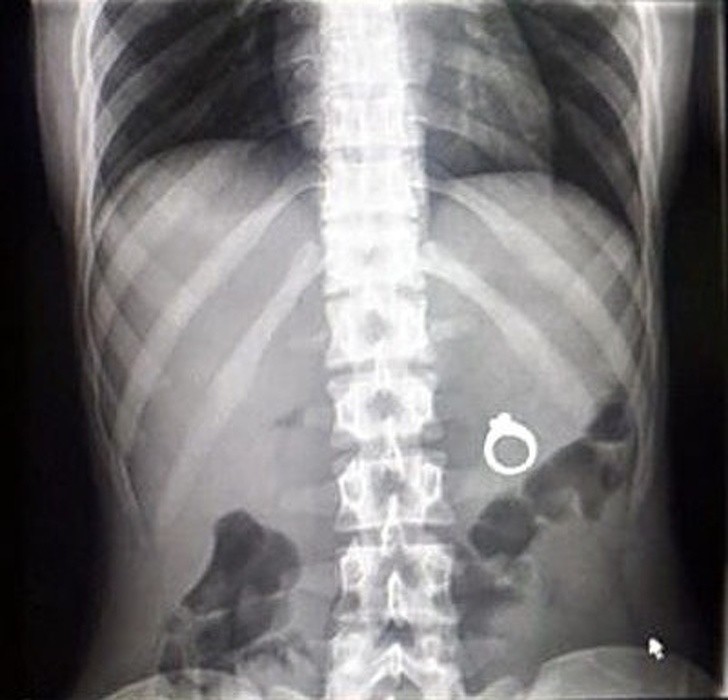

Humans are truly strange creatures and incredibly bizarre things can happen to us. These x-rays will shock even those who think they've seen it all.

X-ray it is one of the best inventions of mankind and in some situations it is indispensable. Especially because it often happens that people, especially children, they swallow objects that are not part of their daily diet. Not to mention the dogs who try to chew everything in sight and thus often end up swallowing inappropriate things.

Radiologists are already quite accustomed to seeing on X-rays strange things and some of these that we have collected for you in the gallery did not surprise them at all. Here is 15+ hacked and sometimes shocking x-rays.